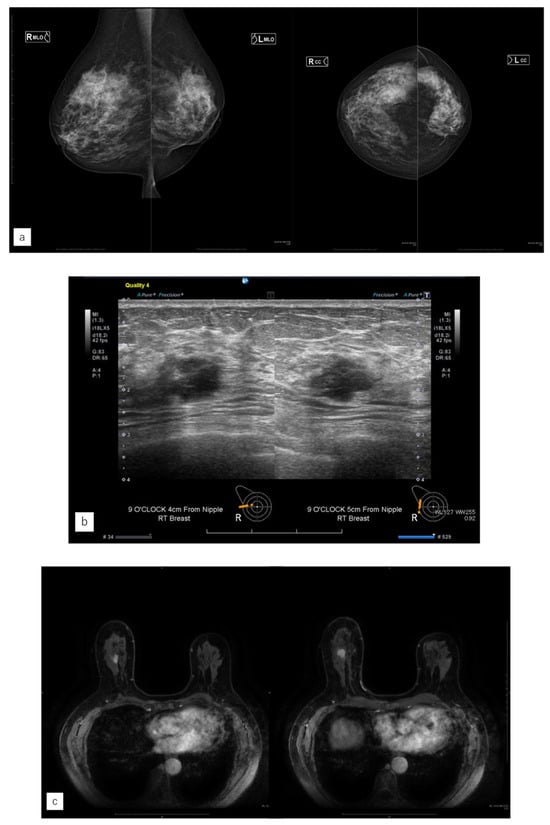

Figure 4.

Representative case (case 1). (a) MG. (b) US. (c) MRI. (d) AI diagnosis. (e) Previous AI diagnosis. A 55-year-old woman had left-sided breast cancer. Eight years later, she was diagnosed with right-sided breast cancer. It was Lumina human epidermal growth factor receptor 2 with 15 mm of invasive cancer and 15 mm of non-invasive cancer. (a) There were no malignant findings on the right side of mammography (MG). (b) Ultrasonography revealed a hypoechoic mass in the right outer area. (c) Magnetic resonance imaging revealed a contrast-enhanced mass measuring 37 mm in the right outer area. (d) The artificial intelligence (AI) system diagnosed malignancy in the right breast based on MG at the time of diagnosis. The malignancy percentage is shown on the left and right sides (CC: right 44.6, left 9.4%, MLO: right 68.9%, left 0.3%). (e) The AI system also showed areas of interest in MG before the diagnosis, and it was diagnosed as possibly malignant. The malignancy percentage of the right side is CC in 77.0% and MLO in 88.5%.